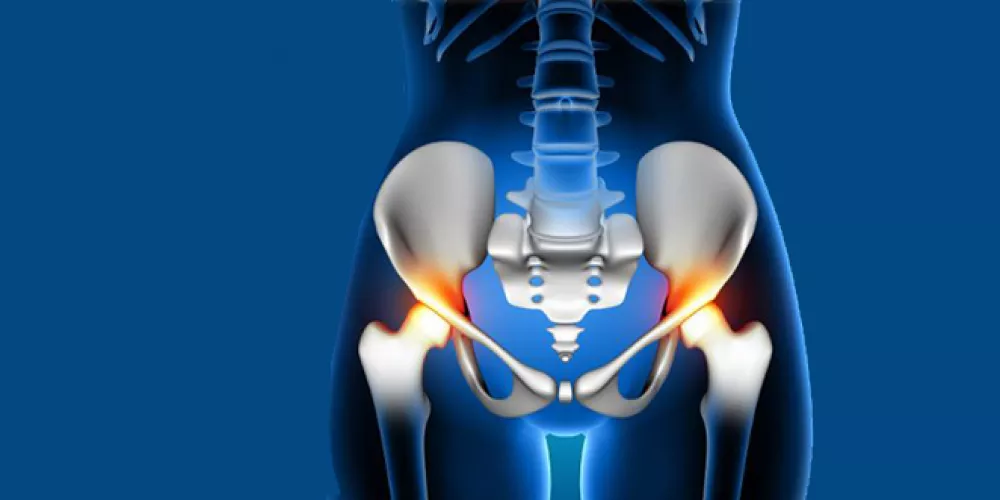

Hip Fracture Surgery, Hip fracture surgery has always been one of the most precise surgical procedures undergone by many people in various cases. It requires a great deal of expertise and skill from the surgical team, along with the use of medical tools. Since this operation is considered somewhat complicated, it requires more attention and preparations. For this reason, readers may benefit from learning more about hip fracture surgery in this article.

Hip Fracture Surgery

Hip fracture surgery is one of the treatment options available for those who have experienced a hip fracture. This procedure can be somewhat challenging, as it sometimes involves making an incision in the skin around the hip area to realign the broken bones. Despite the seriousness of a fracture in the hip area, recovery can take approximately four to six months. The treating orthopedic surgeon will determine the activities the patient should perform during this period.

Causes of Hip Fracture

The causes of hip fractures vary, and they can occur for several reasons, including:

- Falling on the hip.

- Motor vehicle accidents or severe trauma.

- Hip fractures can also result from osteoporosis, which occurs in older adults or those with calcium deficiency.

In cases of hip fracture due to osteoporosis, the condition is diagnosed after experiencing severe pain in the hip area, an inability to move, and in some cases, swelling and redness in the affected area.

When a hip fracture occurs, it can lead to various damages and problems. According to the MSD Medical Guide, one of the main causes of hip fractures is the aging process and bone weakening, which can sometimes lead to nerve damage, negatively affecting a person’s health.

A hip fracture can also result in impaired mobility, physical weakness, urinary system problems, severe pain, and in some rare cases, internal bleeding that can cause significant blood loss, impacting the person’s quality of life.

Hip fracture is considered a serious injury that can lead to impaired mobility, infection, bleeding, and other complications that pose risks to the patient. It is usually caused by falls or severe accidents. Examples of complications from hip fractures include: